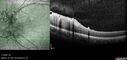

Bullous Retinoschisis - Asymptomatic54 viewsDec 17, 2025

Bullous Retinoschisis - Asymptomatic61 viewsDec 17, 2025

Bullous Retinoschisis - Asymptomatic57 viewsDec 17, 2025